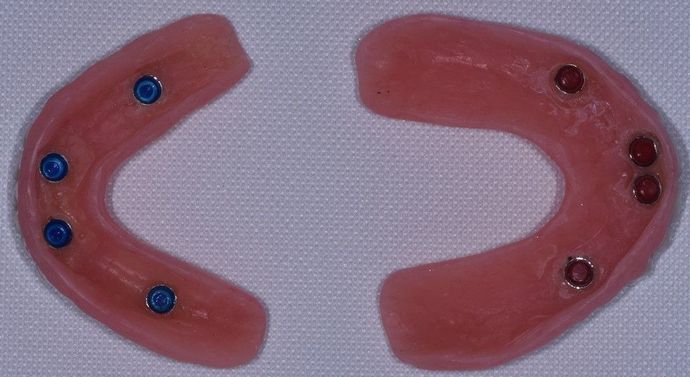

Description

Patient was missing several teeth in both the upper and lower jaw. Her remaining teeth had crowns but all had cavities due to her chronic dry mouth caused by medicines she needed to take. Since she had good quality bone but was prone to cavities, we decided to go with implant supported dentures. She now has the ability to chew again and loves the aesthetic outcome! Also, since we have implant retention on the upper arch, we were able to completely remove the palatal portion of the denture which greatly reduces the bulky feel of the dentures. We love happy patients!